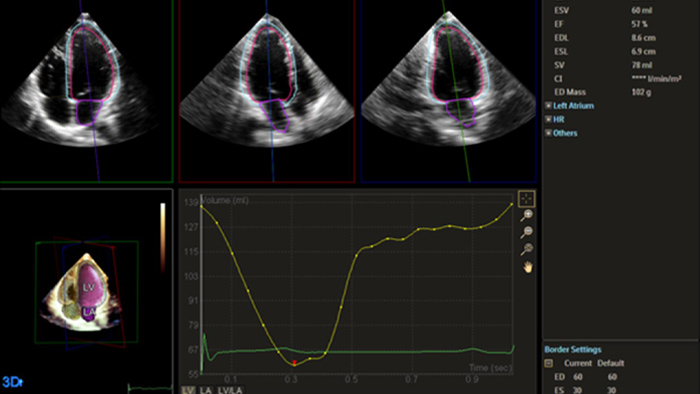

Quantification through Dynamic HeartModel.

Heart failure is prevalent worldwide, and accurate assessment of heart function using echocardiography is essential.1,2 Incorporating strain and 3D assessment of the LV and RV has historically been challenging and required specialized skill sets.

Solution Philips IntelliSpace Cardiovascular multimodality image and information management solution offers a complete look at a patient’s cardiac history. The AI-enabled automation of Philips EPIQ CVx cardiovascular ultrasound system and Philips TOMTEC -ARENA quantification tools provides efficiency and reproducibility during echocardiography studies.